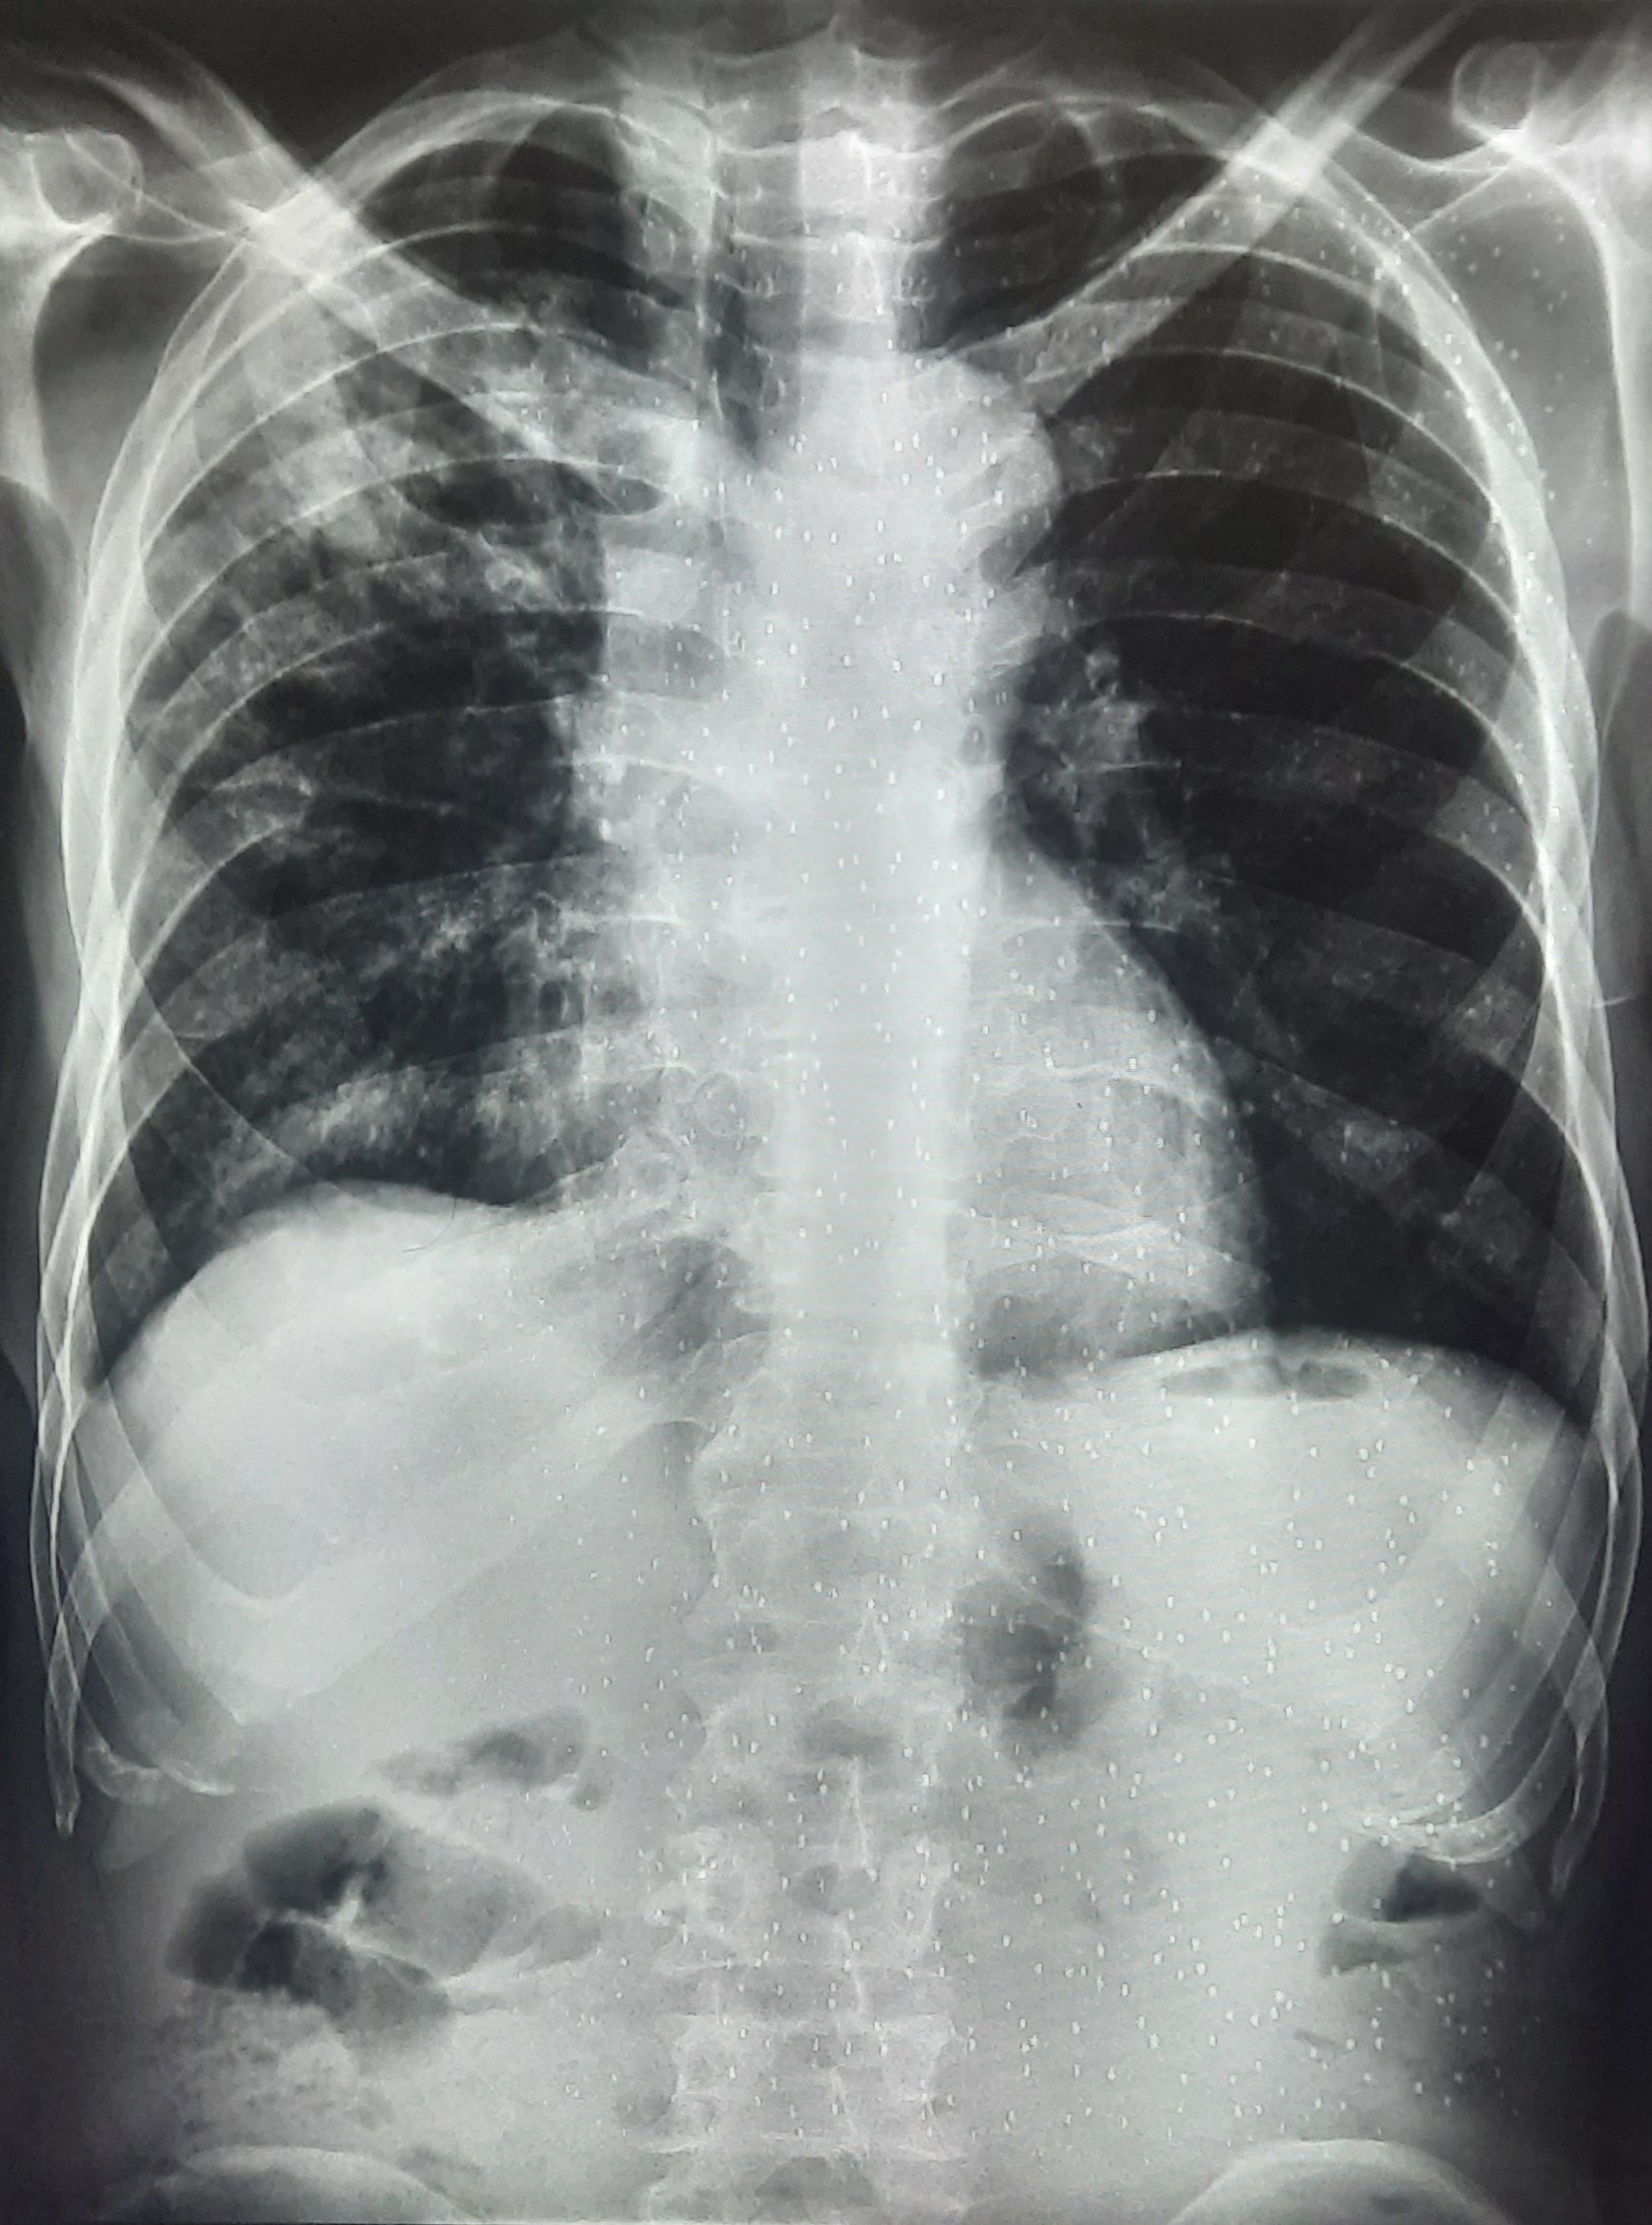

| 297 | IGGMC, Nagpur, Nagpur | P2 | 29-4175 | Sabina Parveen | Consent taken on Paper | 23 Yrs. |

Provisional Diag : PTB Reactivation

Final Diag : ? |

TB Case (Confirmed) | Bilateral Middle Lower Zone Pulmonary TB | Abnormality visible on x-ray |